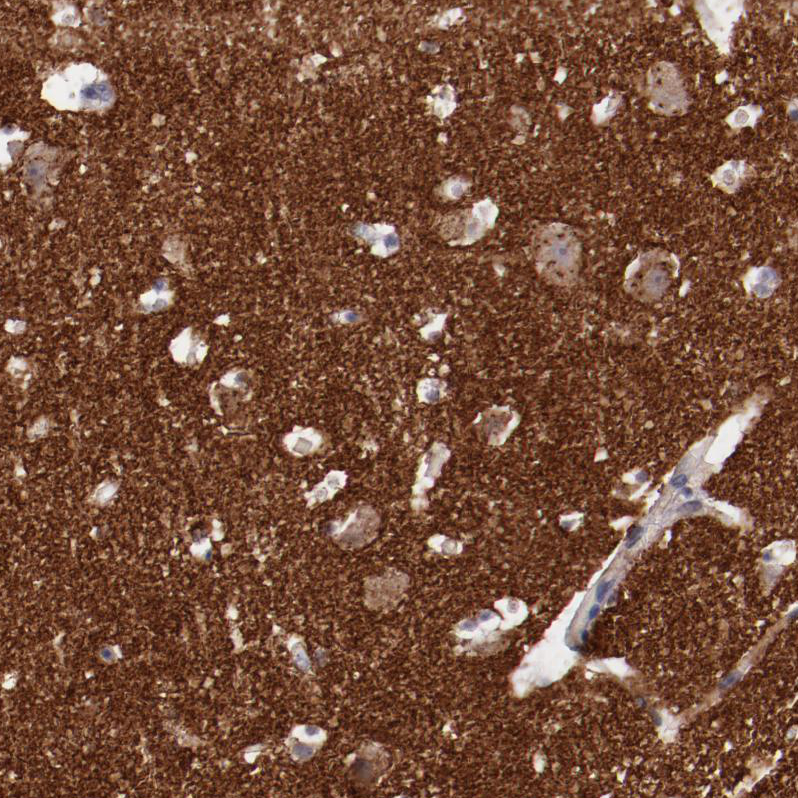

Immunohistochemistry analysis in human cerebral cortex and liver tissues using HPA002858 antibody. Corresponding SYP RNA-seq data are presented for the same tissues.